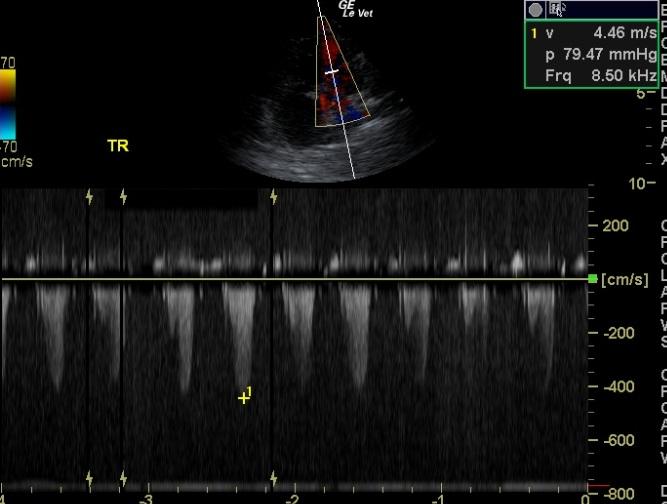

A 10-year-old neutered male Boston Terrier dog was presented for possible seizure activity. A grade II/VI heart murmur and left submandibular lymphadenomegaly were present on physical examination. Abnormalities on CBC and blood chemistry included neutrophilia, eosinopenia, thrombocytosis, elevated ALP activity, and elevated CK. T4 was within normal limits. The patient was treated with enalapril and clindamycin pending ultrasound.